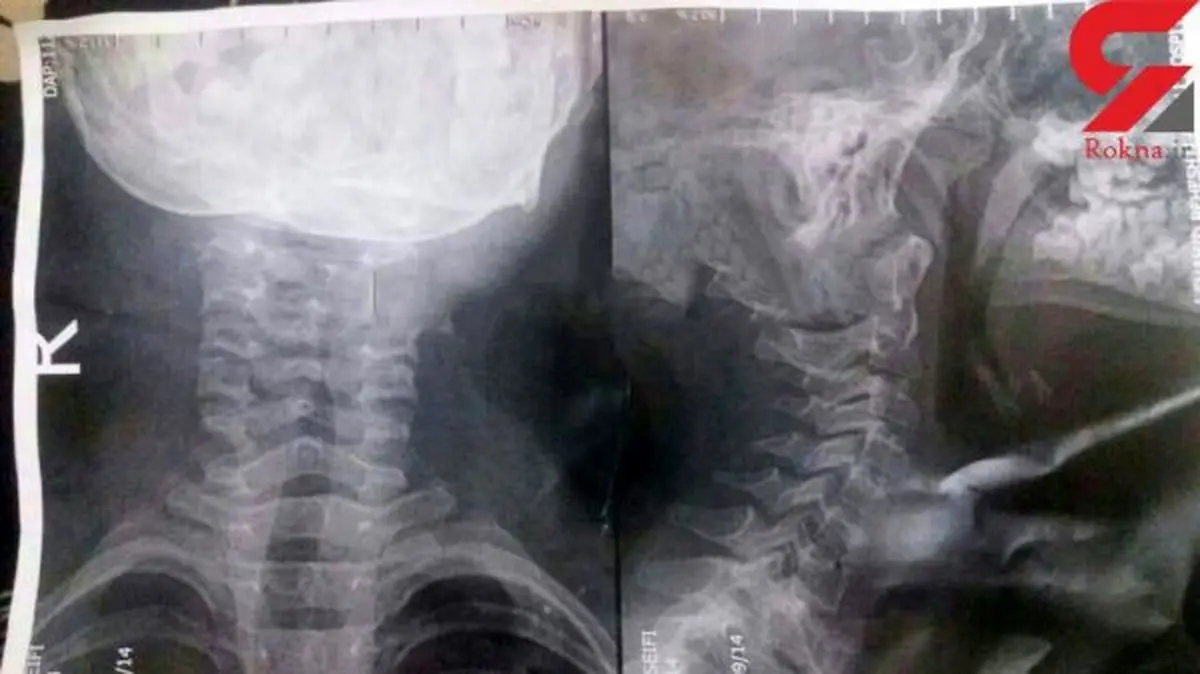

گیر کردن استخوان ماهی در گلوی کودک ۸ ساله گیلانی +عکس

یک پزشک در بندرانزلی با تشخیص اشتباه، جراحی را آخرین درمان برای کودک ۸ساله دانست که استخوان ماهی درگلویش گیر کرده بود، ولی با پافشاری مادر،کودک از زیر تیغ جراحی نجات یافت.

به گزارش سایت خبر فوری به نقل از رکنا؛ کودک 8 ساله سریع به بیمارستان دیگری در رشت انتقال داده شد. جالب اینکه یکی از پزشکان بیمارستان رشت با تشخیص صحیح و به موقع بدون عمل جراحی کودک را فورا درمان کرد.پزشکانی هستند که با بی حوصلگی و عدم تشخیص صحیح باعث خسارات جبران ناپذیری میشوند.